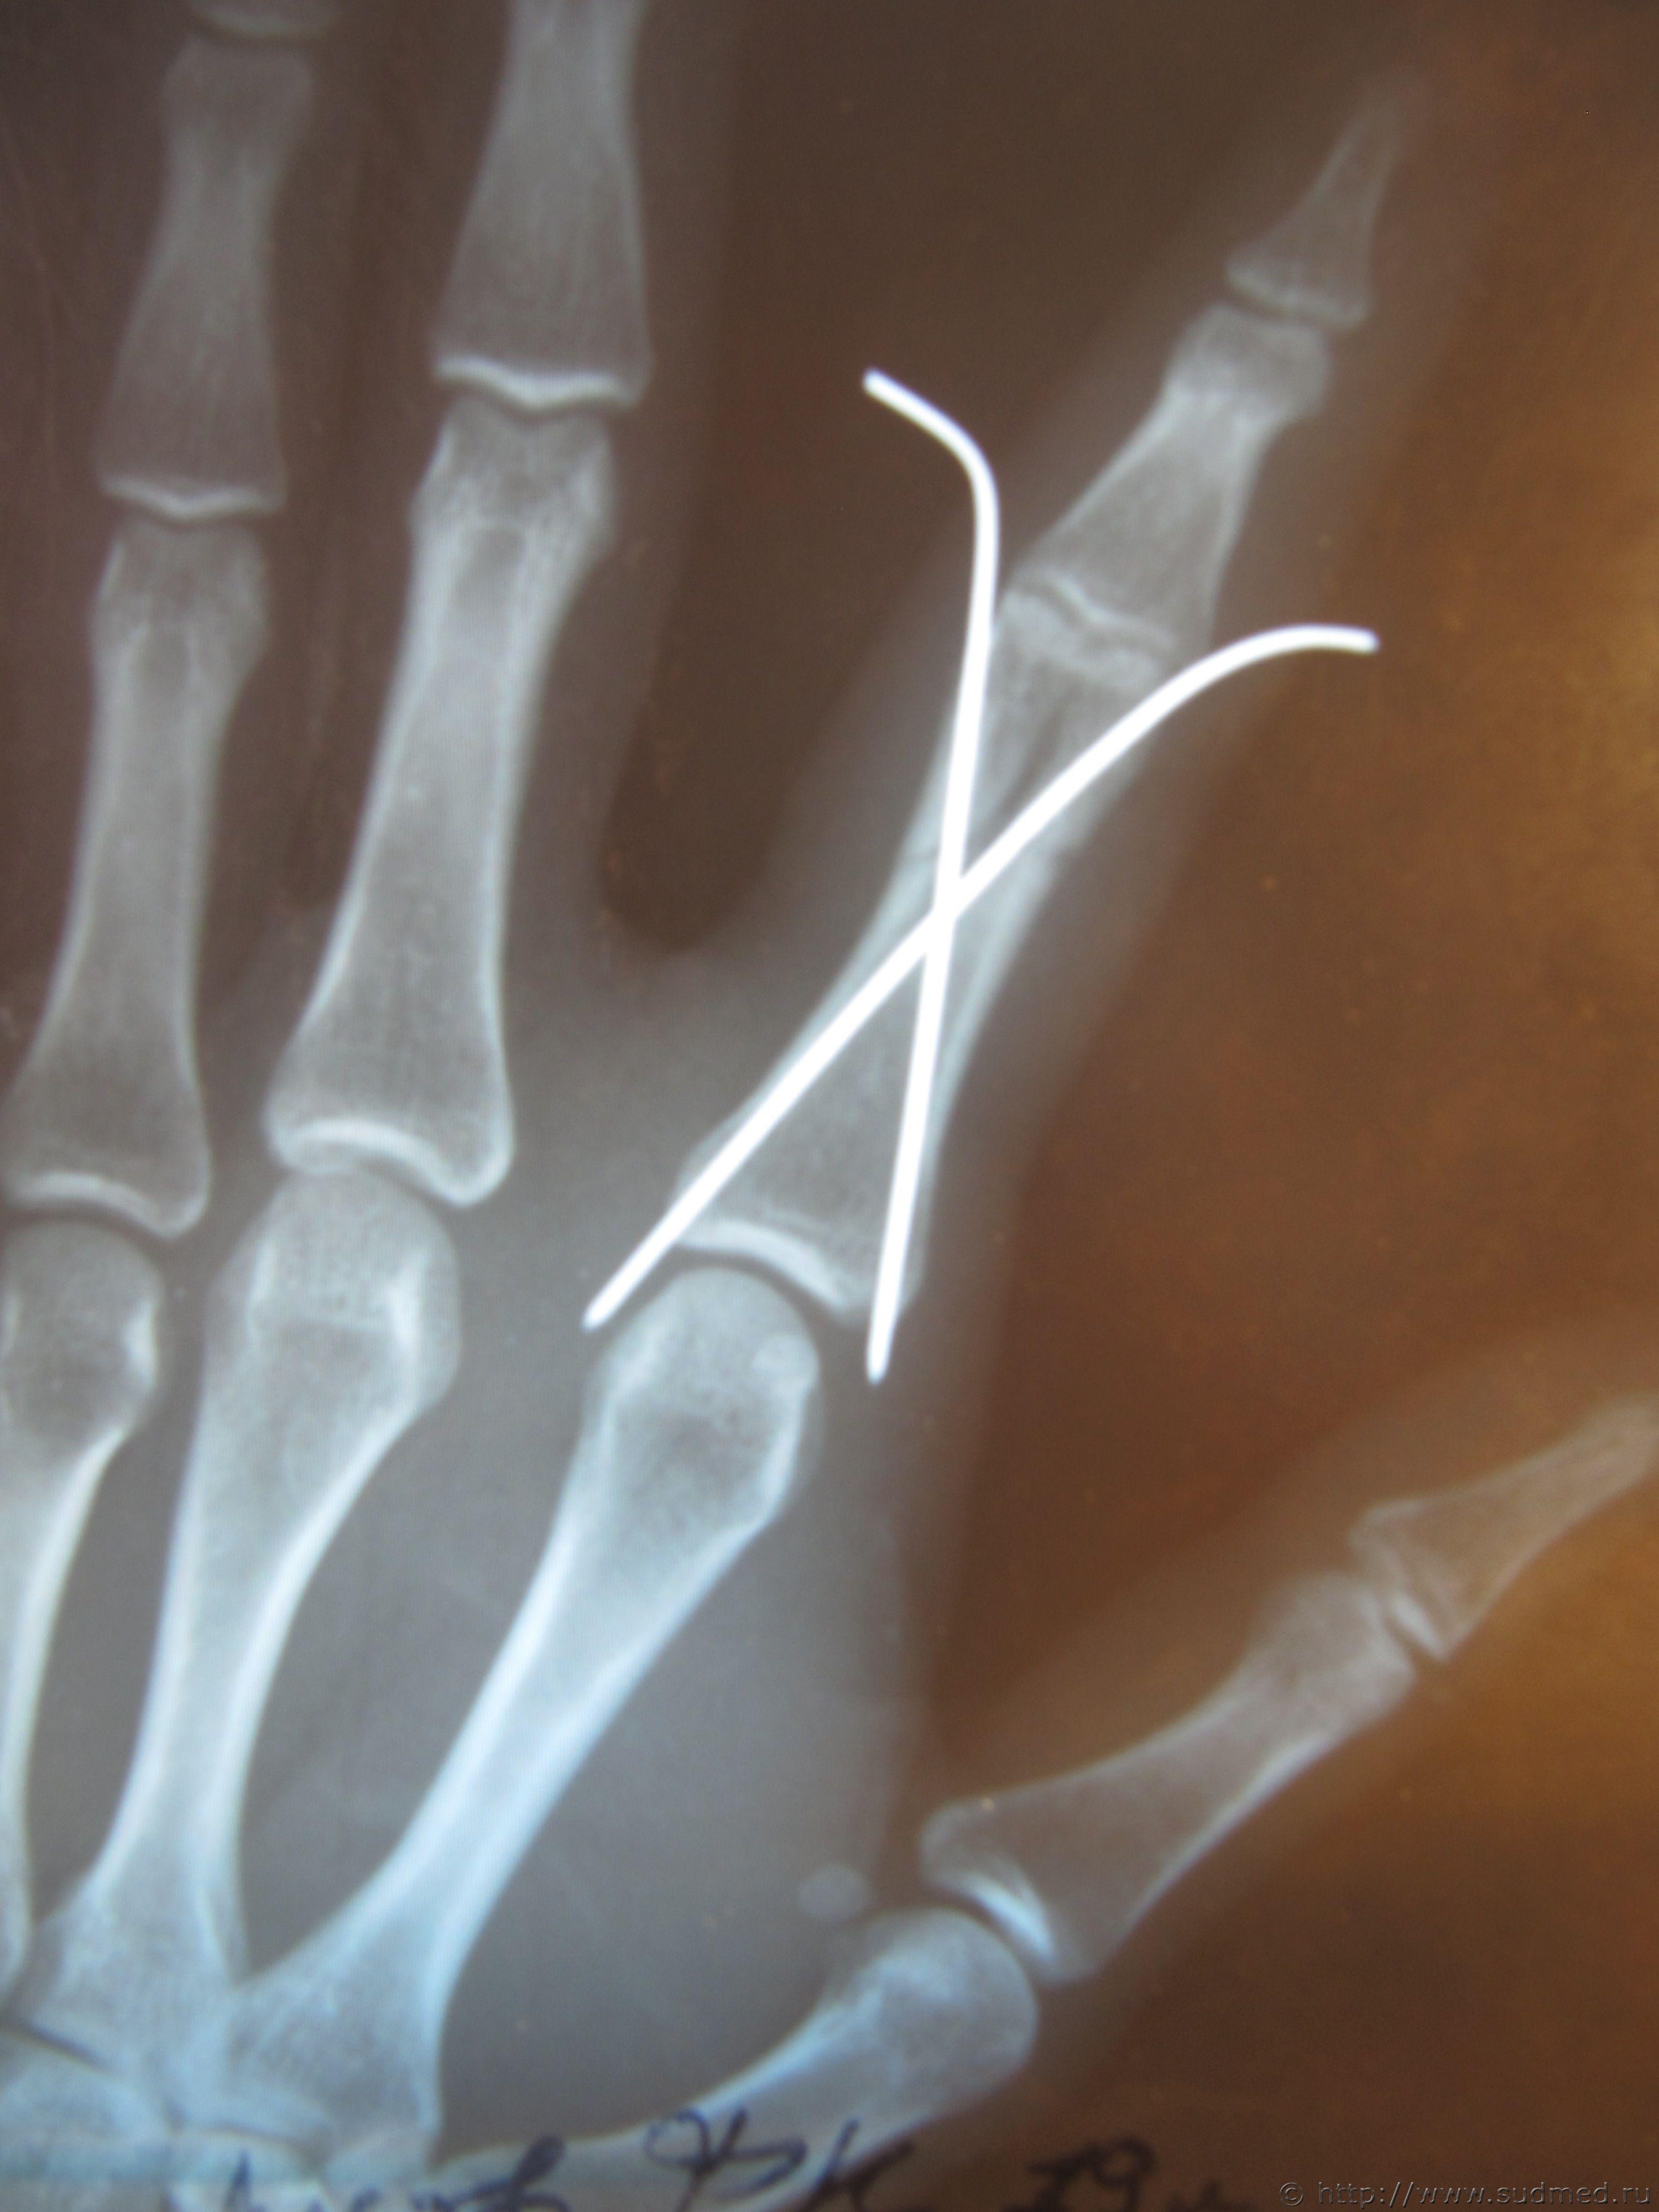

По описанию нашего рентгенолога: перелом нижней трети основной фаланги 2-го пальца правой кисти внутрисуставной оскольчатый Т-образный,к отосланным рентгенограммам, прошу коллег высказать мнение насчет механизма перелома и оценки двух версий

1. выкрутили пальцы 2. удар кулаком по лицу Эскизы прикрепленных изображений |

Радомир В прямой проекции - перелом классически Т-образный... 2.05.2011 - 23:46